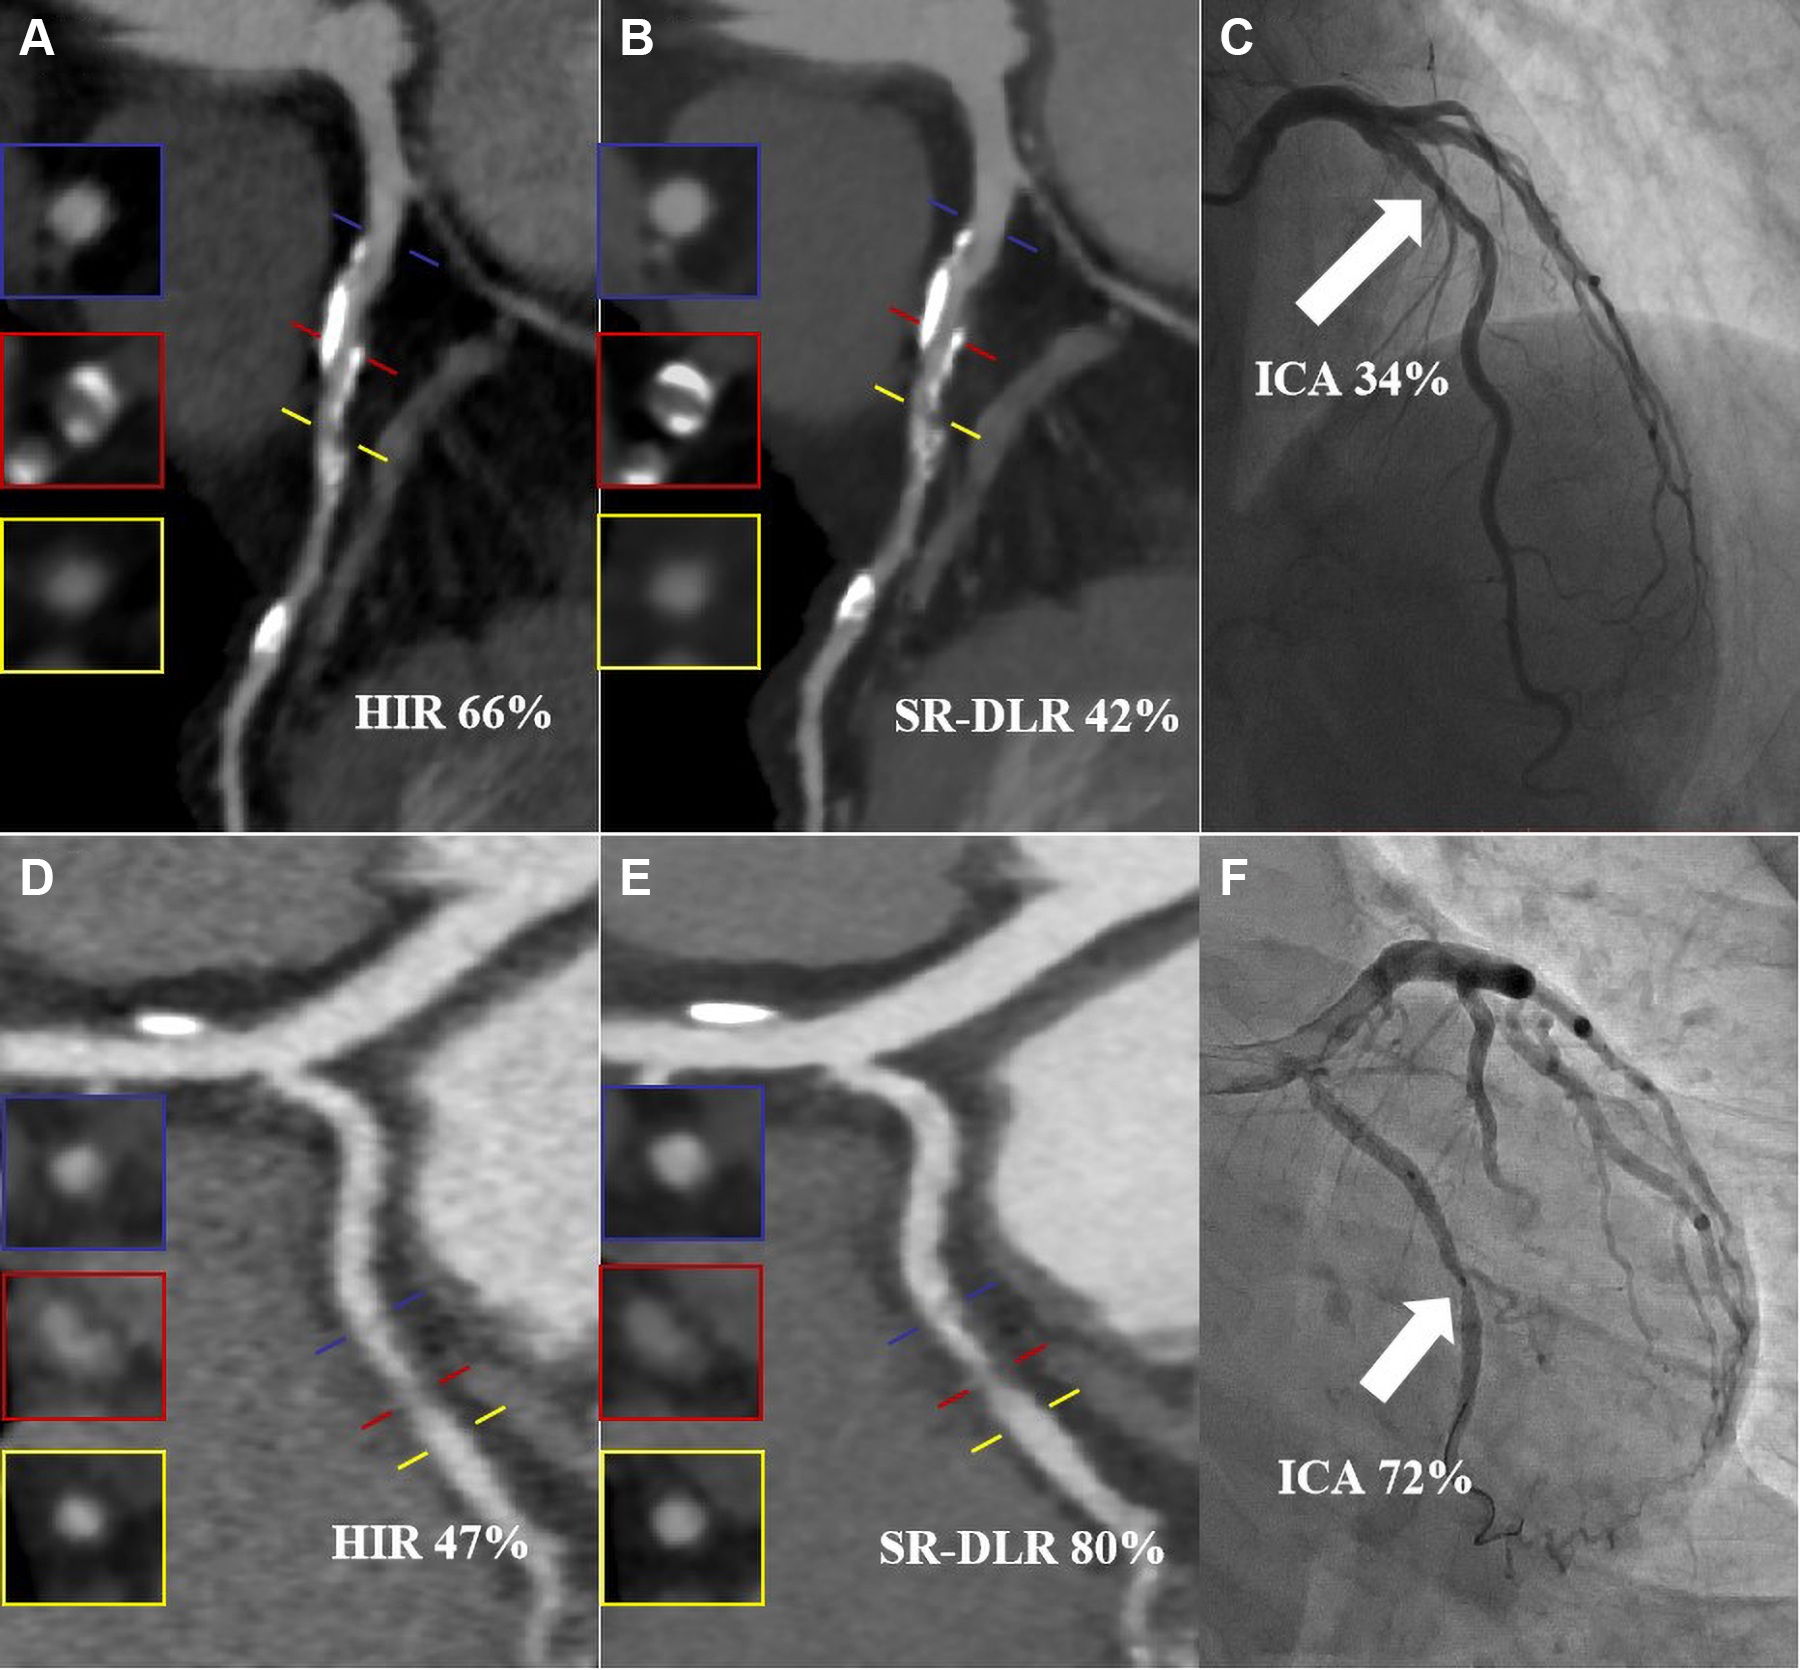

Giuseppe ScappaturaMRIDoes patient anxiety influence MRI contrast extravasation?In anxious patients, the MRI environment can sustain or amplify activation of the sympathetic nervous system.January 22, 2026ResourcesThe Portal of ImagesGiuseppe Scappatura wrote "The Portal of Images" to help children understand CT exams.September 10, 2025ResourcesSofia and the Magic MachineGiuseppe Scappatura wrote "Sofia and the Magic Machine" to help children understand MRI procedures.September 10, 2025Page 1 of 1Top StoriesCTSuper-resolution deep learning reconstruction improves CCTAThe commercially available image reconstruction algorithm outperformed standard hybrid iterative reconstruction for assessing coronary stenosis.Womens ImagingNonsurgical management rising for low-risk DCIS casesMRIGadoxetate MRI offers high sensitivity for liver cancer screeningMRIPodcast: MRI service engineer faced nightmare with man's entrapmentMolecular ImagingPET/CT visualizes complications in patients on hemodialysis